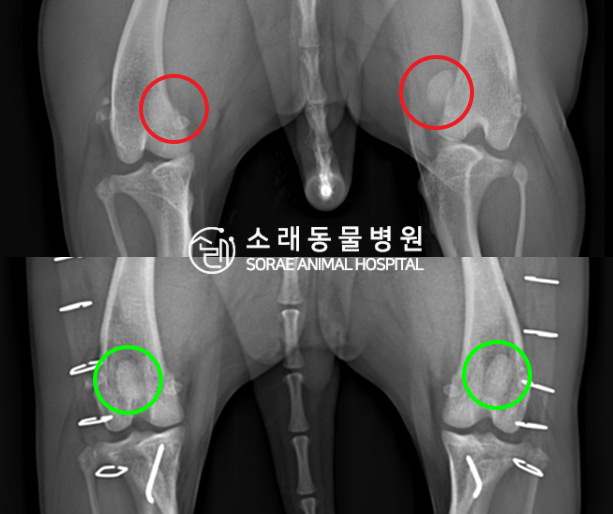

수술전과 수술후에 촬영한 봉지의 슬개골

방사선 사진입니다. 나란히 놓고 비교해보니

슬개골의 위치에 확연한 차이가 있는 것을

확인해 볼 수 있는데요. 내측으로 탈구되어 있던

슬개골이 원래 제자리인 활차구에 예쁘게

자리 잡고 있는 모습을 확인할 수 있었습니다.